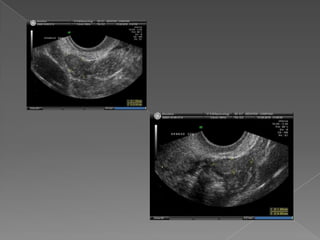

 RN ypre-púber : forma tubular Cuerpo/cuello :relación 1/1 o menor  Útero RN: 1cm mayor que la lactante  Pre-púber : 3 cm x 2 cm x 2 cm.  Adulta : 7,5 cm x 5 cm x 2,5 cm  Tamaño varia con paridad , post- parto y estabiliza con 1,5 cm de aumento.